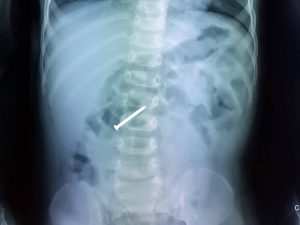

Một trường hợp tai nạn trẻ nhỏ nuốt phải cây đinh dài 3cm vừa được các bác sĩ Bệnh Viện Đa Khoa Xuyên Á (BVXA) xử trí nhanh chóng, gắp dị vật ra thành công.